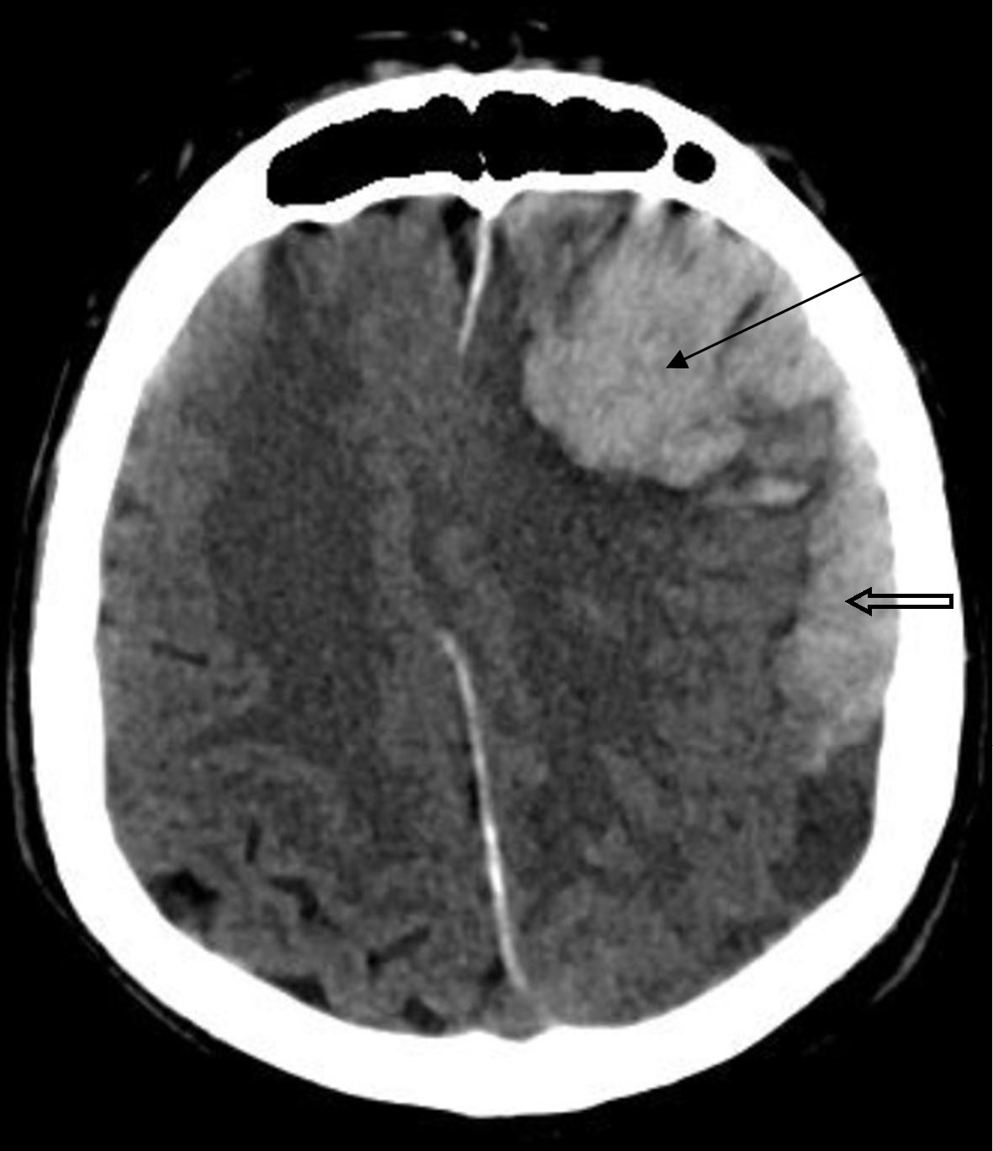

COVID-19 patients are at an increased risk of brain tissue damage. The injury of heart or brain tissue can be caused via 4 different pathways. These include the neuronal pathway, the hypoxia pathway, the renin–angiotensin–aldosterone system (RAAS) pathway, and the immune pathway. Patients with comorbidities are a high-risk group and need to be kept under careful observation. In case brain hemorrhage is suspected, CT or magnetic resonance imaging (MRI) should be performed (Figure 9).32 Medical imaging is an essential tool in screening and localizing life-threatening COVID-19.